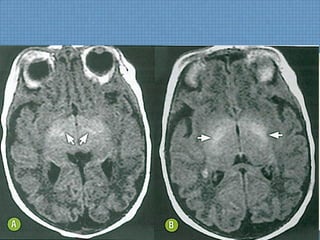

ACHADOS DE IMAGEM

• TC:

– Muito limitada;

• RM:

– Atrofia cerebral e cerebelar;

– Perda da interface SB-SC;

– Hiperssinal T2/FLAIR simétrico em pedúnculos cerebelares

médio e braço posterior da cápsula interna;

– Afilamento do corpo caloso;

– Hiperssinal de SB também pode ser visto;

Hipossinal em T2 em núcleos denteados cerebelares,

tálamo, SN e núcleos rubros indica deposição de Fe;

INTOXICAÇÃO POR TOLUENO

INTOXICAÇÃO POR

TOLUENO